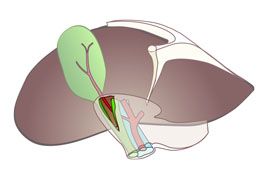

• Laparoskopische Cholezystektomie

Inhalt des Kurses ist das Erlernen der laparoskopischen Grundtechniken wie die systematische diagnostische Laparoskopie, die laparoskopische Appendektomie und Cholezystektomie sowie das laparoskopische Nähen. Der Kurs ist für Ärzte in der Facharztausbildung im Fach Allgemein- und Viszeralchirurgie vorgesehen. An dem Tübinger Trainer werden an Organkomplexen die Operationen schrittweise trainiert. Die manuellen Übungen sind in steigenden Schwierigkeitsgraden von Basistechniken bis hin zu komplexen Nahttechniken aufgebaut.

Sie werden unterstützt durch theoretische Einweisungen in die angewendeten medizinischen Instrumente, Koagulationsgeräte sowie in die Klammernahtgeräte und Knüpftechniken. Nach Abschluss des Kurses soll der Teilnehmer in der Lage sein, selbstständig unter der Assistenz eines Facharztes die laparoskopische Appendektomie und laparoskopische Cholezystektomie durchzuführen.